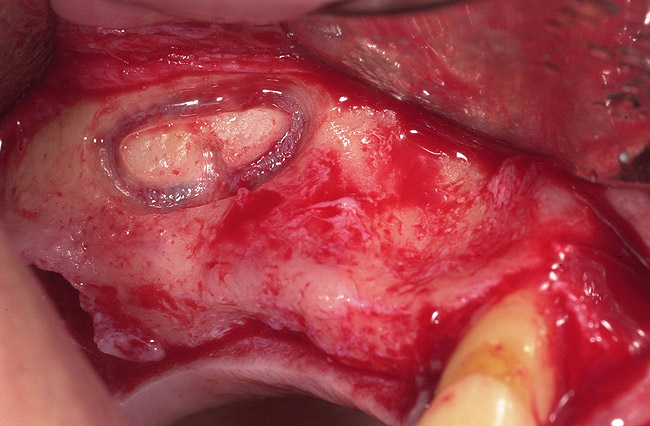

Figure 1  Buccal and radiographic views of posterior edentulism with significant sinus pneumatization in the molar region.

Figure 1

Figure 2  Buccal and radiographic views of posterior edentulism with significant sinus pneumatization in the molar region.

Figure 2